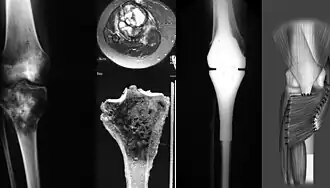

La tumeur est solide, dure, irrégulière, (décrite en « sapin » ou en « rayon de soleil » sur les examens aux rayons X) en raison des spicules tumorales d'os calcifiés rayonnant en angle droit. Ces angles droits forment ce que l'on appelle un triangle de Codman. Les tissus environnants sont infiltrés.

Le diagnostic de cette pathologie est suggéré à l’aide de techniques d’imageries comme la radiographie, l’IRM, la scintigraphie osseuse, la tomodensitométrie, puis confirmé par biopsie[11],[12].

- un retrait de la zone tumorale par chirurgie, voire une amputation du membre concerné, avec possible pose de prothèse remplaçant l'os. Il peut aussi être envisagé de faire une reconstruction par lambeau libre à la suite de l’exérèse ou dans le même temps opératoire[14];